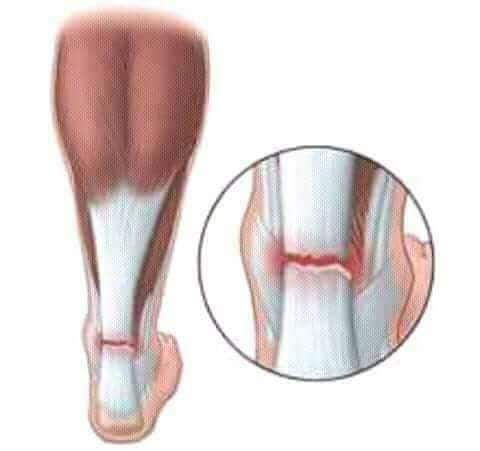

Тендинит Ахиллова сухожилия: симптомы и лечение

Раздел: Картинки на заметку